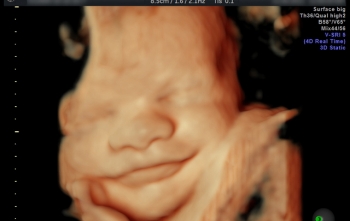

No ConquistaCom deste sábado, a Sonnar destacou a importância do exercício físico na Gestação, em entrevista com o ginecologista/obstetra e ultrassonografista Clodoaldo Cadete. Quais os indicados e quais os contraindicados?